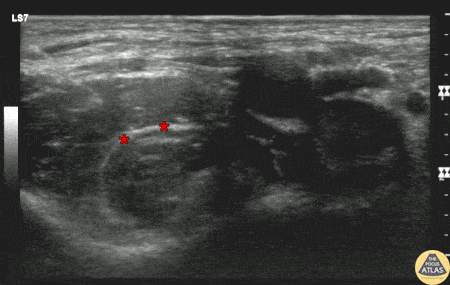

A teenaged male patient presented with hip pain and inability to ambulate after a fall off of an electric scooter. XRs demonstrated an intertrochanteric femur fracture, and CT ruled out other involvement of the pelvis or femoral head. To provide analgesia, a fascia iliaca block was performed. Shown here, the needle enters from the lateral aspect, lateral to the femoral nerve, artery, and vein which are seen at the top right of the image. Anesthetic is spread along the fascial plane shown (*). This patient had improved pain and was able to be admitted to the floor for surgery the next day. Dr. Lee Johnson, PGY2 Denver Health Residency in Emergency Medicine